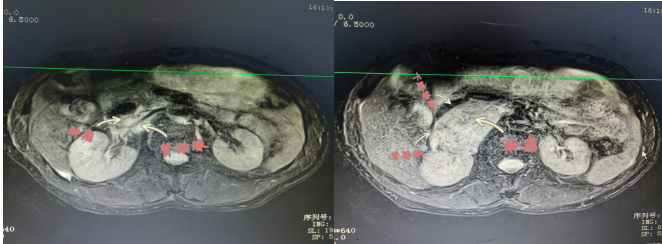

患者陽某,67歲,8月2日因“反復胸悶氣促2年余,再發(fā)伴頭暈黑蒙3天?!本驮\于衡陽市中心醫(yī)院心血管內(nèi)科,患者血壓波動大,最高值199/118mmHg,最小值98/57mmHg,射血分數(shù)最低42%;完善相關檢查發(fā)現(xiàn)右腎上腺巨大腫物,大小約57×73×75mm,遂轉(zhuǎn)入衡陽市中心醫(yī)院泌尿外科治療,泌尿外科醫(yī)護團隊前期做了充分的準備,并進行科內(nèi)討論,麻醉科、心血管內(nèi)科專家會診,充分予以穩(wěn)定血壓、心率和擴容等術前處理。

2022年9月15日,醫(yī)院為患者行腹腔鏡下右側(cè)腎上腺瘤腫瘤切除術,術中,患者右側(cè)腎上腺腫瘤于腎門,壓迫下腔靜脈,右腎靜脈移位,包繞右腎動脈。腫瘤體積大,血運豐富與周圍組織邊界不清, 與大血管粘連,手術風險極大,術中鉗夾,擠壓腎上腺瘤體導致腎上腺激素釋放,手術中血壓的急劇變化。充分顯露手術視野,仔細、輕柔操作對腫瘤切除十分關鍵。麻醉科主任譚滇湘全程護航。由于準備充分、配合到位,雖術中情況多變,最終手術成功。術后病檢結(jié)果顯示腫瘤完整切除?;颊咝g后恢復良好,于2022年9月24康復出院。